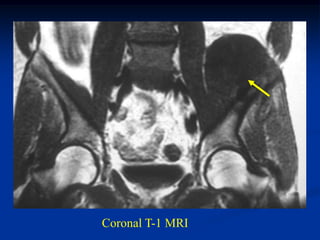

Case #1125

65 year male with path fracture thru metastatic renal cell CA

in sciatic notch area